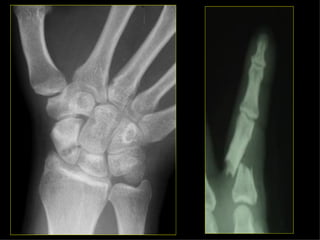

HOMBRO BRAZO CODO ANTEBRAZO MUÑECA MANO Monteggia Colles Fx escafoides

HOMBRO BRAZO CODOANTEBRAZO MUÑECA MANO Monteggia Colles Fx escafoides